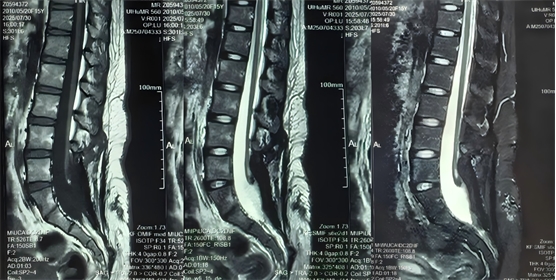

圖2為此次手術(shù)前復(fù)查腰骶椎MR檢查,提示脊髓拴系松解滿意